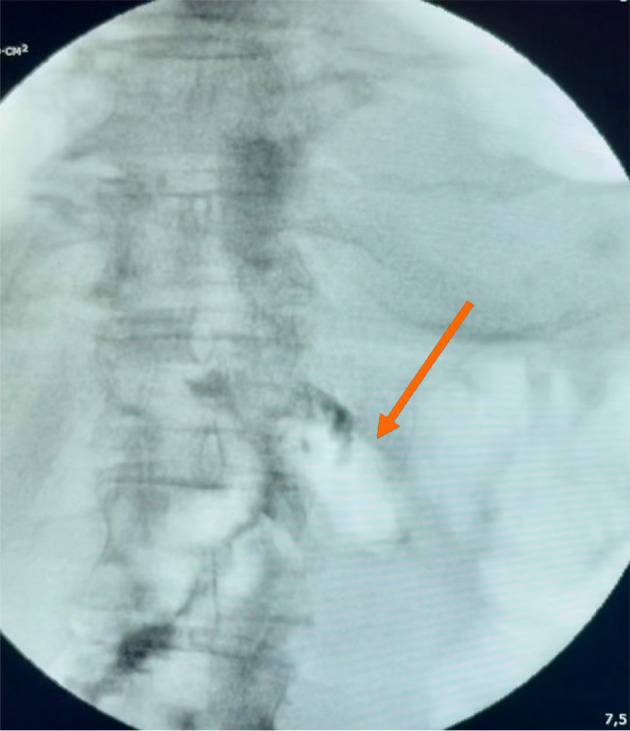

Case summary: We present two cases of patients who underwent total gastrectomy for gastric malignancy. A combined therapeutic approach was employed, based on isolating the injury site with local vacuum-assisted closure (VAC) therapy and simultaneous enteral nutrition. This method facilitated successful healing and enabled the identification of previously undetected defects not recognized by conventional diagnostics.